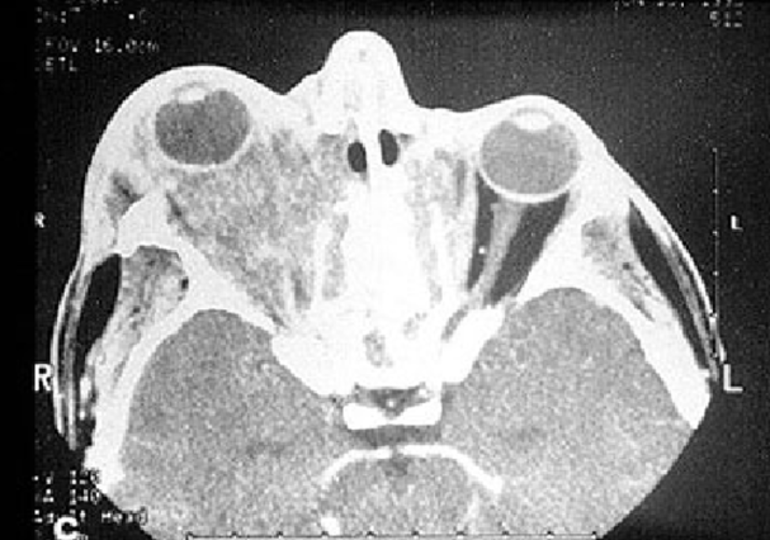

У некоторых пациентов может развиться мастоидит — воспалительный процесс в области височной кости, находящейся за ухом, который приводит к нарушениям слуха и восприятия звуков, связанным с васкулитом. В области глаз данная патология проявляется язвами на роговице, которые могут перейти в кератит и увеит. У таких пациентов возникают светобоязнь, отечность век, ухудшение остроты зрения и слезотечение. Хронический кератит может привести к перфорации роговицы, что, в свою очередь, может вызвать слепоту. Также нарушение кровоснабжения зрительного нерва может иметь серьезные последствия.

Раннее выявление гранулематоза представляет собой сложную задачу, поскольку на начальных этапах пациенты часто принимают симптомы заболевания за обычную простуду или грипп и редко обращаются за медицинской помощью. Первым шагом в диагностике является тщательный опрос и осмотр пациента для выявления симптомов. При наличии подозрений на болезнь Вегенера рекомендуется консультация у ревматолога, а также проведение лабораторных и инструментальных исследований, таких как рентгенография, ультразвуковое обследование и томография.